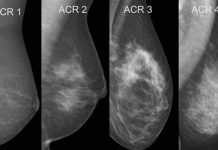

Exame de tomossíntese se mostra o mais eficiente para diagnosticar câncer de mama